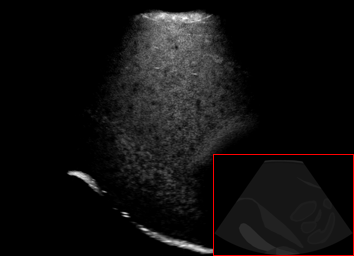

Real in-vivo images. 22 ultrasound sequences were collected using a GE Voluson E8 machine during standard fetal screening exams of 8 patients. Each sequence is several seconds long. We extracted all 4427 frames and resize them to , see Fig. 2 for some examples. The resulting image set was randomly split into training-validation-test sets by a 80-10-10% ratio.

US simulation. We used a ray-tracing framework to render B-mode images from a geometric fetal model, by simulating a convex probe placed at multiple locations and orientations on the abdominal surface, with imaging settings listed in Tab 1. At each location, simply rasterizing a cross-section through the triangulated anatomical surfaces at the ultrasound center imaging plane provided corresponding semantic maps. Fig. 3 shows example B-mode images with corresponding semantic maps. A total of simulated frames were resized to and randomly split into training-validation-test sets by 80-10-10%.